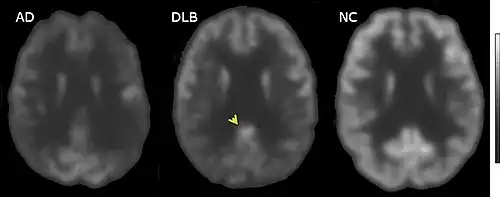

Medical imaging in AD and DLB

MRI of brain showing hippocampus atrophy (red rectangles), more prominent in AD than DLB, compared to normal control (NC)

FDG-PET horizontal cross section of brain, with brighter areas indicating higher metabolism. The cingulate island sign is indicated by the arrowhead.

FDG-PET of brain surface, with the color red indicating areas of high metabolism. The occipital lobe in DLB (arrows) shows less activity than in AD.

PET or SPECT imaging can be used to detect reduced dopamine transporter uptake and distinguish AD from DLB.[56][144] Severe atrophy of the hippocampus is more typical of AD than DLB.[145] Before dementia develops (during the mild cognitive impairment phase), MRI scans show normal hippocampal volume. After dementia develops, MRI shows more atrophy among individuals with AD, and a slower reduction in volume over time among people with DLB than those with AD.[32] Compared to people with AD, FDG-PET brain scans in people with DLB often show a cingulate island sign.[32]